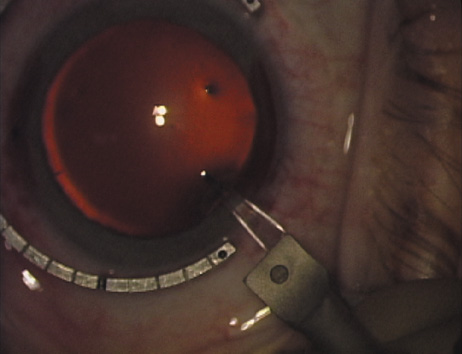

Case 3 is a 48-year-old bilateral hyperope who presented for a refractive surgical consultation. The refraction in his left eye was found to be +3.25 +1.75 × 85. Keratometry was somewhat flat but confirmed WTR cylinder as did corneal topography. Based upon the patient's age, refraction, and somewhat shallow anterior chambers, the decision was made to proceed with a refractive lens exchange. The NAPA nomogram called for LRIs of 55 to 60 degrees with intraoperative pachymetry. Intraoperative keratoscopy confirmed the steep 85-degree meridian (Figs. 2029).

Fig. 20. Keratoscopy, after lifting of the speculum to relieve induced pressure and distortion of the corneal mires, confirms the steep axis of 85 degrees.

Fig. 21. The broad hash marks of the fixation ring are centered just off of the 6:00 limbal orientation mark, over the 85 degree meridian in this left eye. The two cut RK marker is positioned at one extent of the LRI, just under 30 degrees from the central steep meridian and the cornea is marked.

Fig. 22. A second mark is made delineating the opposite extent for a total arc length of just under 60 degrees.

Fig. 23. Following pachymetry measurement over the entire arc length of the incision, an adjustable micrometer diamond knife is set to 90% of the thinnest reading obtained.

Fig. 24. The inferior incision is begun.

Fig. 25. The incision is completed for a total arc length of just under 60 degrees.

Fig. 26. The opposing superior LRI is begun.

Fig. 27. The incision is completed at the corneal mark.

Fig. 28. 6A side-port incision is created for the surgeon's non-dominant right hand, taking care not to intersect the LRI.

Fig. 29. The single-plane RLE incision is completed.